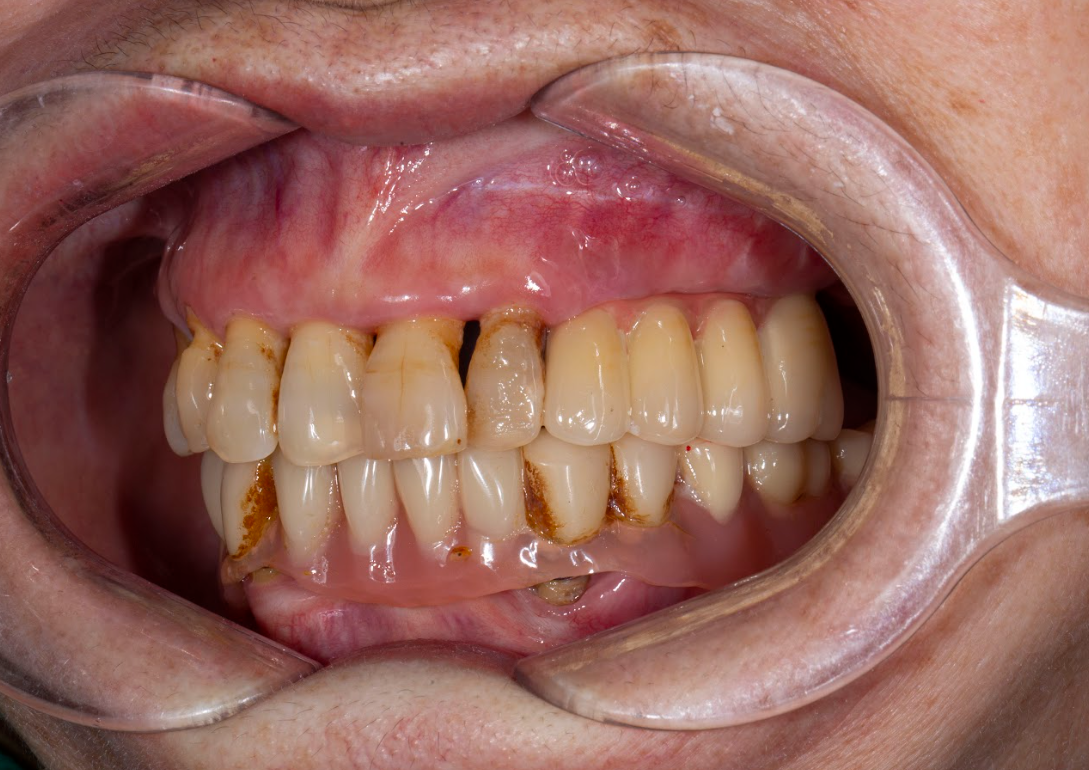

Kết quả sau điều trị – “Tôi không còn phải truyền chất nữa”

Chỉ sau một thời gian ngắn, tình trạng của cô thay đổi rõ rệt:

Không còn phải truyền dinh dưỡng, có thể tự ăn uống đầy đủ.

Tăng cân trở lại, cải thiện sức khỏe tổng thể.

Ăn được nhiều loại thức ăn: thịt, rau, hoa quả… mà trước kia phải kiêng.

Tinh thần phấn chấn, vui vẻ, giao tiếp tự tin.

-

“Mỗi chiếc răng được trồng giống như thêm một phần sức khỏe được hồi sinh” – cô Cúc chia sẻ.